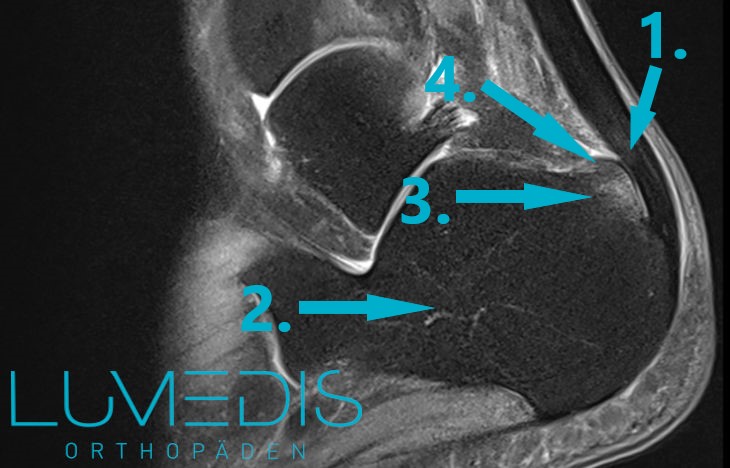

Abbildung (Anatomie) der Außenbänder am Knöchel (Bänderriss)

MRT T2 OSG nach einer Umknickverletzung